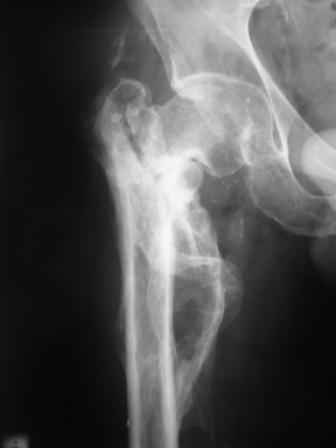

Больной Н. 44 года травма 1,5 года назад июнь 2008 года чрез-под вертельный перелом правого бедра. Во время лечения у больного развился алк. делирий, проводилось консервативное лечение перелома.

Беспокоят боли, укорочение конечности.Укорочение 3 см. Ногу поднимает, сгибание ограничено, ротационные движения в полном объеме.На КТ перелом сросся за счет костной мозоли.Что делать?

Протез? Если «да» Можно ли обойтись стандартной ножкой Corail?

Или межвертельная остеотомия?